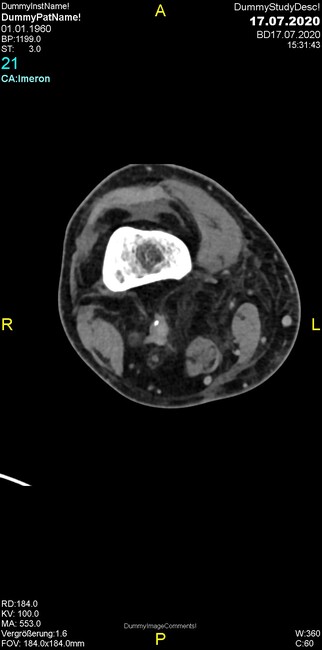

Um welche Modalitäten handelt es sich?

- Röntgen p.a. und lateral, CT coronar Knochenfenster, CT axial Weichgewebsfenster

- Röntgen p.a. und lateral, CT coronar Weichgewebsfenster, MR axial

Was fällt in der Projektionsradiographie auf?

- Verdichtung im Recessus suprapatellaris

- Aufhellungslinie in Projektion auf die Femurkondylen

- Erhöhter tibialer Slope

- Hypertransparenz tibial

- Subluxationsstellung im Kniegelenk

Was trifft auf den Befund zu?

- Der Befund beschränkt sich auf den Knochen.

- Es besteht hochakuter Handlungsbedarf.

- Der Befund ist tendenziell benigne.

- Der Befund ist tendenziell maligne.

- Der Befund weist einen Zusammenhang zum Patientenalter auf.

Was fällt in der CT im Knochenfenster auf?

- Mediale Gelenkspaltverschmälerung

- Dezente Erosion der fibulären Kortikalis

- Frakturspalt der lateralen Tibiametaphyse

- Weichgewebskalzifikationen lateral angrenzend an den Gelenkspalt

- Osteolyse der Tibiametaphyse unter Beteiligung der Kortikalis

Was kommt differentialdiagnostisch in Frage?

- Kompartmentsyndrom

- Osteomyelitis mit Weichgewebsanteil

- Metastase mit pathologischer Fraktur

- Rheumatoide Athritis

- Posttraumatische Verletzung